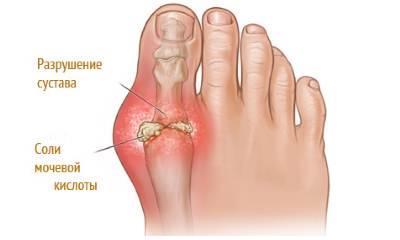

Во время течения заболевания происходит накапливание производных мочевой кислоты (кристаллы уратов) в суставах, тканях, органах и других системах организма. Нарушение целостности сустава (частичное или полное разрушение) происходит из-за того, что урат кристаллизуется и откладывается в виде мелких частичек.

Фото: подагра на большом пальце ноги у мужчины

Помимо того, что больных беспокоит сильнейшая боль, во время приступа сустав начинает распухать, краснеть, кожа в этой области становится ярко-красной или багряной, теплой или горячей на ощупь. Даже незначительное прикосновение к воспаленному месту или минимальное движение в суставе причиняют невыносимую боль. После нескольких дней мучительной боли (3-4 дня) симптомы резко прекращаются, будто ничего и не было.